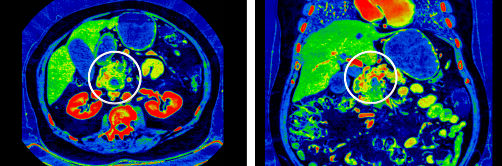

VUE

Iodine color maps. Virtual Unenhanced images (VUE) – The HU values in the VUE images were similar to the HU values in the non-contrast images which can assess anatomy potential masked by contrast and provide reliable information for characterizing diverse lesions. VUE benefits for radiation oncology6: VUE potentially may be used for lesion characterization, avoiding the error of registration when contrast enhancement requires: accurate target delineation and dose calculations.

Effective-Z map

Effective-Z (effective atomic number) generated by GSI is accurate2 and closely related to diverse tissue electron density. Eff-Z map may help to illustrate tissue distribution. The accuracy of proton stopping-power ratio (SPR) prediction is dependent on the ability to correctly characterize patient tissues. Conventional CT HU-SPR conversion has limitations in dealing with human tissue diversity.1 Effective-Z map benefits for radiation oncology: Eff-Z may be used for prediction in proton therapy, with the potential1,3,4 to reduce uncertainties in particle range prediction5 and improve accuracy of dose planning.